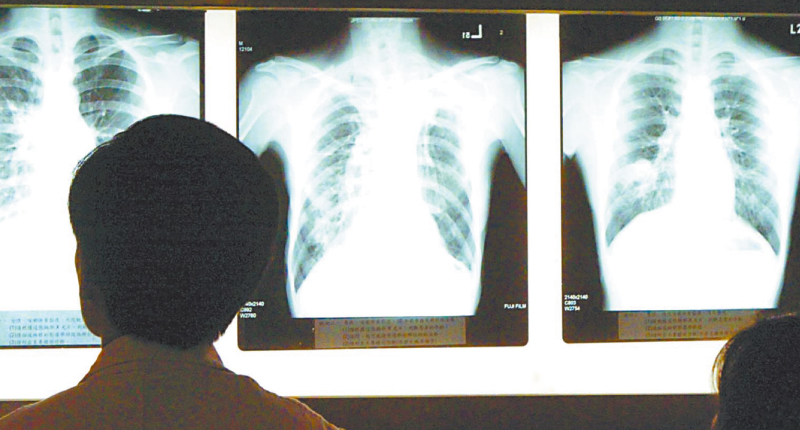

通報中也提到,病例臨床表現主要為發熱,少數病人呼吸困難,胸片呈雙肺浸潤性病灶。目前,所有病例均已隔離治療,密切接觸者的追蹤調查、醫學觀察,以及對華南海鮮城的衛生學調查、環境衛生處置均正在進行當中。相關病毒分型檢測、隔離治療、終末消毒等工作也同步展開。